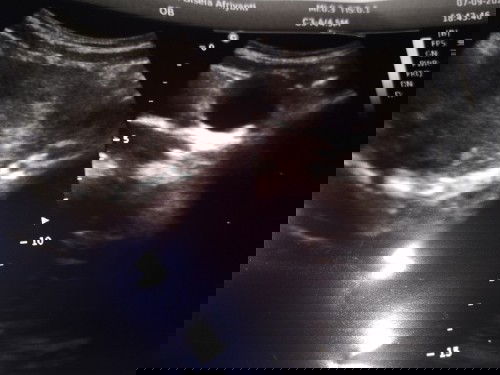

Bun wajar ga si kehamilan jalan 7 minggu baru keliatan kantong janin nya saja makasi

memang kalo 7 minggu keatas baru keliatan kantongnya aja mom, nanti kalo udh tm2 baru keliatan ada isinya